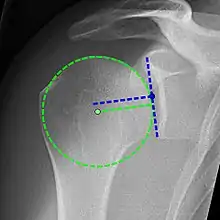

Xray

X-ray projectional radiography cannot directly reveal tears of the rotator cuff, a 'soft tissue', and consequently, normal X-rays cannot exclude a damaged cuff. However, indirect evidence of pathology may be seen in instances where one or more of the tendons have undergone degenerative calcification (calcific tendinitis). The humeral head may migrate upwards (high-riding humeral head) secondary to tears of the infraspinatus, or combined tears of the supraspinatus and infraspinatus.[47] The migration can be measured by the distance between:

- A line crossing the center of a line between the superior and inferior rims of the glenoid articular surface (blue in image).

- The center of a "best-fit" circle positioned over the humeral articular surface (green in image)

Normally, the former is positioned inferiorly to the latter, and a reversal is therefore indicating a rotator cuff tear.[47] Prolonged contact between a high-riding humeral head and the acromion above it, may lead to X-rays findings of wear on the humeral head and acromion and secondary degenerative arthritis of the glenohumeral joint (the ball and socket joint of the shoulder), called cuff arthropathy, may follow.[46] Incidental X-ray findings of bone spurs at the adjacent acromioclavicular joint may show a bone spur growing from the outer edge of the clavicle downwards towards the rotator cuff. Spurs may also be seen on the underside of the acromion, once thought to cause direct fraying of the rotator cuff from contact friction, a concept currently regarded as controversial.